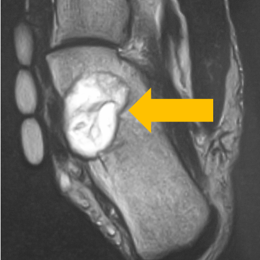

Radiographic imaging is used to help form a diagnosis of CMF. These include, X-Ray, MRI, CT and Bone Scans. An example of a CMF MRI is shown.